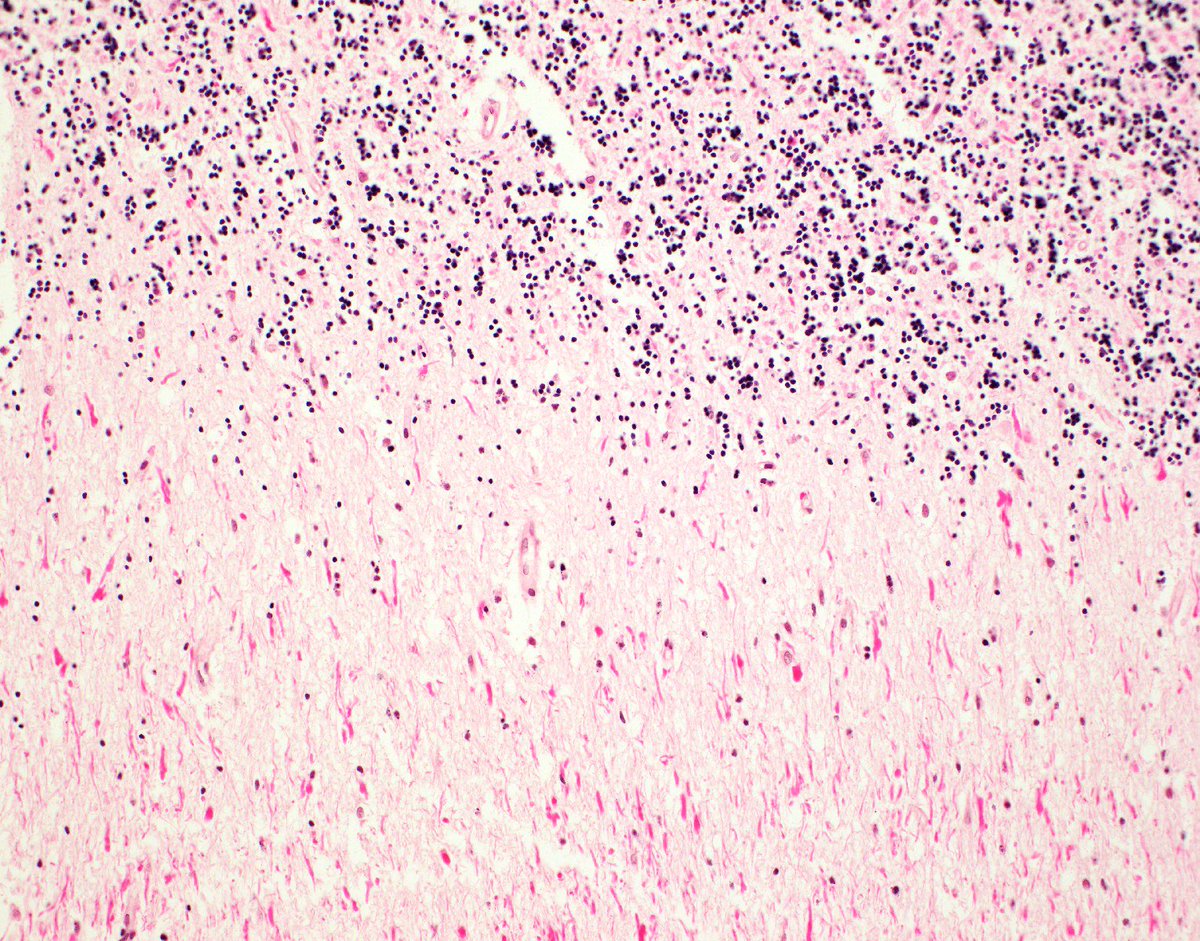

MARIBEL DONASTORG VITTINI Pembe Oltulu, MD The dx is T-cell lymphoblastic lymphoma. Not all starry sky pattern is Burkitt.

@bansar_bansaria Woo Cheal Cho, MD Bin Xu Sanjay Mukhopadhyay Jerad Gardner, MD Kalyani Bambal Xiaoyin "Sara" Jiang, MD (She/Her) @DrFNA Vijay Shankar S Bunina bodies in motor neurons of the anterior horn in ALS